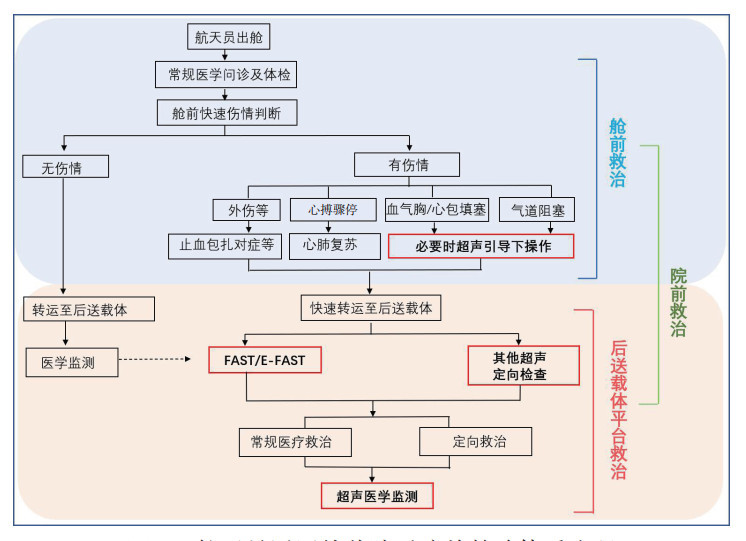

1.2 航天员返回院前医疗救护流程航天员出舱后的院前医疗救治环节,主要分为两大部分:

⑴舱前救治,主要进行伤情快速的筛查及处置,通过简单问诊、查体初步确定伤情,如果无明显伤情,则要求快速的将航天员送入后送载体中(如直升机或医监医保救护车),进行进一步伤情的排查;如出现开放性创伤,如颅脑、四肢外伤,则在舱前进行快速、简单的止血、包扎等处理后立即后送。如出现严重伤情,导致生命体征不能维持或心搏骤停,则按照急救预案,立即在舱前紧急剖开航天服,展开胸外按压、心肺复苏等措施,如出现危及生命的血气胸、心包填塞,可立即在舱前超声引导下行紧急胸腔或心包穿刺,如遇到难以经口插管的气道阻塞的伤情,可在超声的指导下行环甲膜穿刺,进行紧急气道开放。特别是情况紧急、周围环境干扰较大,容易导致定位不准,胸腔穿刺及环甲膜穿刺操作困难。便携超声引导可准确定位、缩短操作时间,避免盲目操作风险,减少并发症[12]。一旦条件允许,立即后送。

⑵后送载体平台救治,航天救护中所用后送载体主要为直升机和地面医监医救车,直升机是航天医疗救护的首选载体。如遇特殊地形或极端天气,直升机不能起飞或无法降落,医监医救车可第一时间进入现场展开救治运送。直升机作为重要的战场急救医疗救护的载体之一,转送速度快,受地形影响小,在野战医疗急救中发挥了重要作用,直升机医疗急救体系(helicopter emergency medical services, HEMS)在降低创伤患者病死率方面与地面医疗急救体系(ground emergency medical services, GEMS)疗效一致,但比地面救治转运距离更远[13],从而为伤情的急救及后送赢得了宝贵的时间,已成为空间站任务院前急救中的主体。但直升机内强大的噪声,不利于临床医生进行常规心肺听诊等物理检查,因此近几年提出了直升机重点超声检查(point-of-care ultrasound, PoCUS)概念[14],即以直升机作为急救平台,在直升机上进行快速且有针对性的超声探查,研究显示在直升机上所获得的超声影像的质量并不劣于地面救治[15]。故在后送载体内运用FAST或E-FAST的快速筛查法,可行性强,是快速发现如钝性腹部创伤、血气胸等一些引起的血流动力学不稳定的隐匿伤情的可靠方法[16],为院前救治(图 1)赢得宝贵时间。

|

| 图 1 航天员返回舱着陆后院前救治体系流程 |

|

|

【推荐意见1】航天员返回后在院前迅速进行伤情评估,如出现重大伤情,可根据伤情具体情况,运用便携超声开展指导性诊治。Fast/E-Fast伤情快速判断及排查或相关超声医学监测,建议在后送载体中实施;舱前不建议仅以诊断为目的的超声检查。